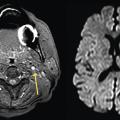

Une prise en charge en urgence des AIT de moins de 48 h diminue de près de 80 % le risque de récidive d’AVC. La conduite doit être identique lors d’un TVT supposé d’origine ischémique. Cela implique de réaliser dans l’idéal une IRM cérébrale + ARM des TSA (fig. 2) dépistant un patient à haut risque de récidive (angioscanner si contre-indication ou échodoppler des troncs supra-aortique [TSA] et transcrânien [TC]) et de débuter en urgence un traitement adéquat : endartériectomie pour une sténose carotidienne symptomatique ≥ 70 % (bénéfice prouvé par l’étude NASCET, même s’il est moindre que pour les AIT), anticoagulant pour une FA, antiagrégant (simple par aspirine ou double avec dose de charge pour les AIT à haut risque ou AIC mineur) et statine en cas d’atteinte athéromateuse.

Il est possible de stratifier le risque d’AVC après un AIT selon le score ABCD2 et l’IRM cérébrale couplée à une angio-IRM (ARM) des vaisseaux du cou et intracrânienne. De même, lors d’ischémies rétiennes constituées ou transitoires, l’IRM cérébrale est positive en diffusion dans près de 25 % des cas ; il s’agit de lésions ischémiques punctiformes, associées à une cause à haut risque de récidive (sténose serrée, dissection carotidienne ou cardiopathie emboligène). Cet examen serait positif dans 11 % des CMT (fig. 1). Dans le service SOS AIT de Bichat, 34,4 % des patients avaient des TVT dont 50 % isolés. L’IRM était positive dans 5,9 % des cas (11,8 % si hémianopsie latérale homonyme ; cette dernière était plus souvent associée à une FA : × 2,5 par rapport aux AIT sans TVT).